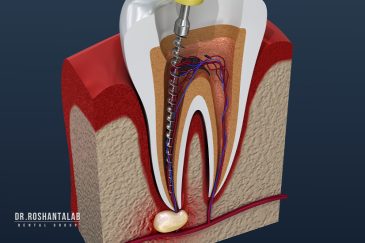

🔸 کاشت ایمپلنت دندان بدون درد

🔸کاشت ایمپلنت فلپ لس یا بدون جراحی و بدون بخیه زیر سه دقیقه

🔸 کاشت دندان یک روزه ( کشیدن و کاشت همزمان )